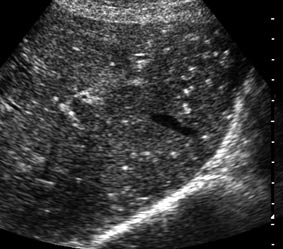

Наиболее вероятные варианты: хронический холангит, мелкие конкременты внутрипеченочных желчных протоков, холестероз.

на некоторый картинках - действительно - мелкие конкременты желчных ходов,

на других - просто перифокальные изменения стенок сосудов.